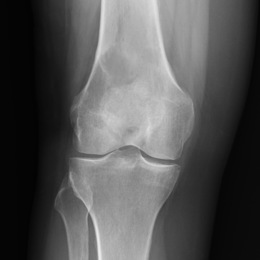

102A) Plain AP Xray Of Right Femur MFH

Screen Shot 2022 08 19 At 11.26.50 AM